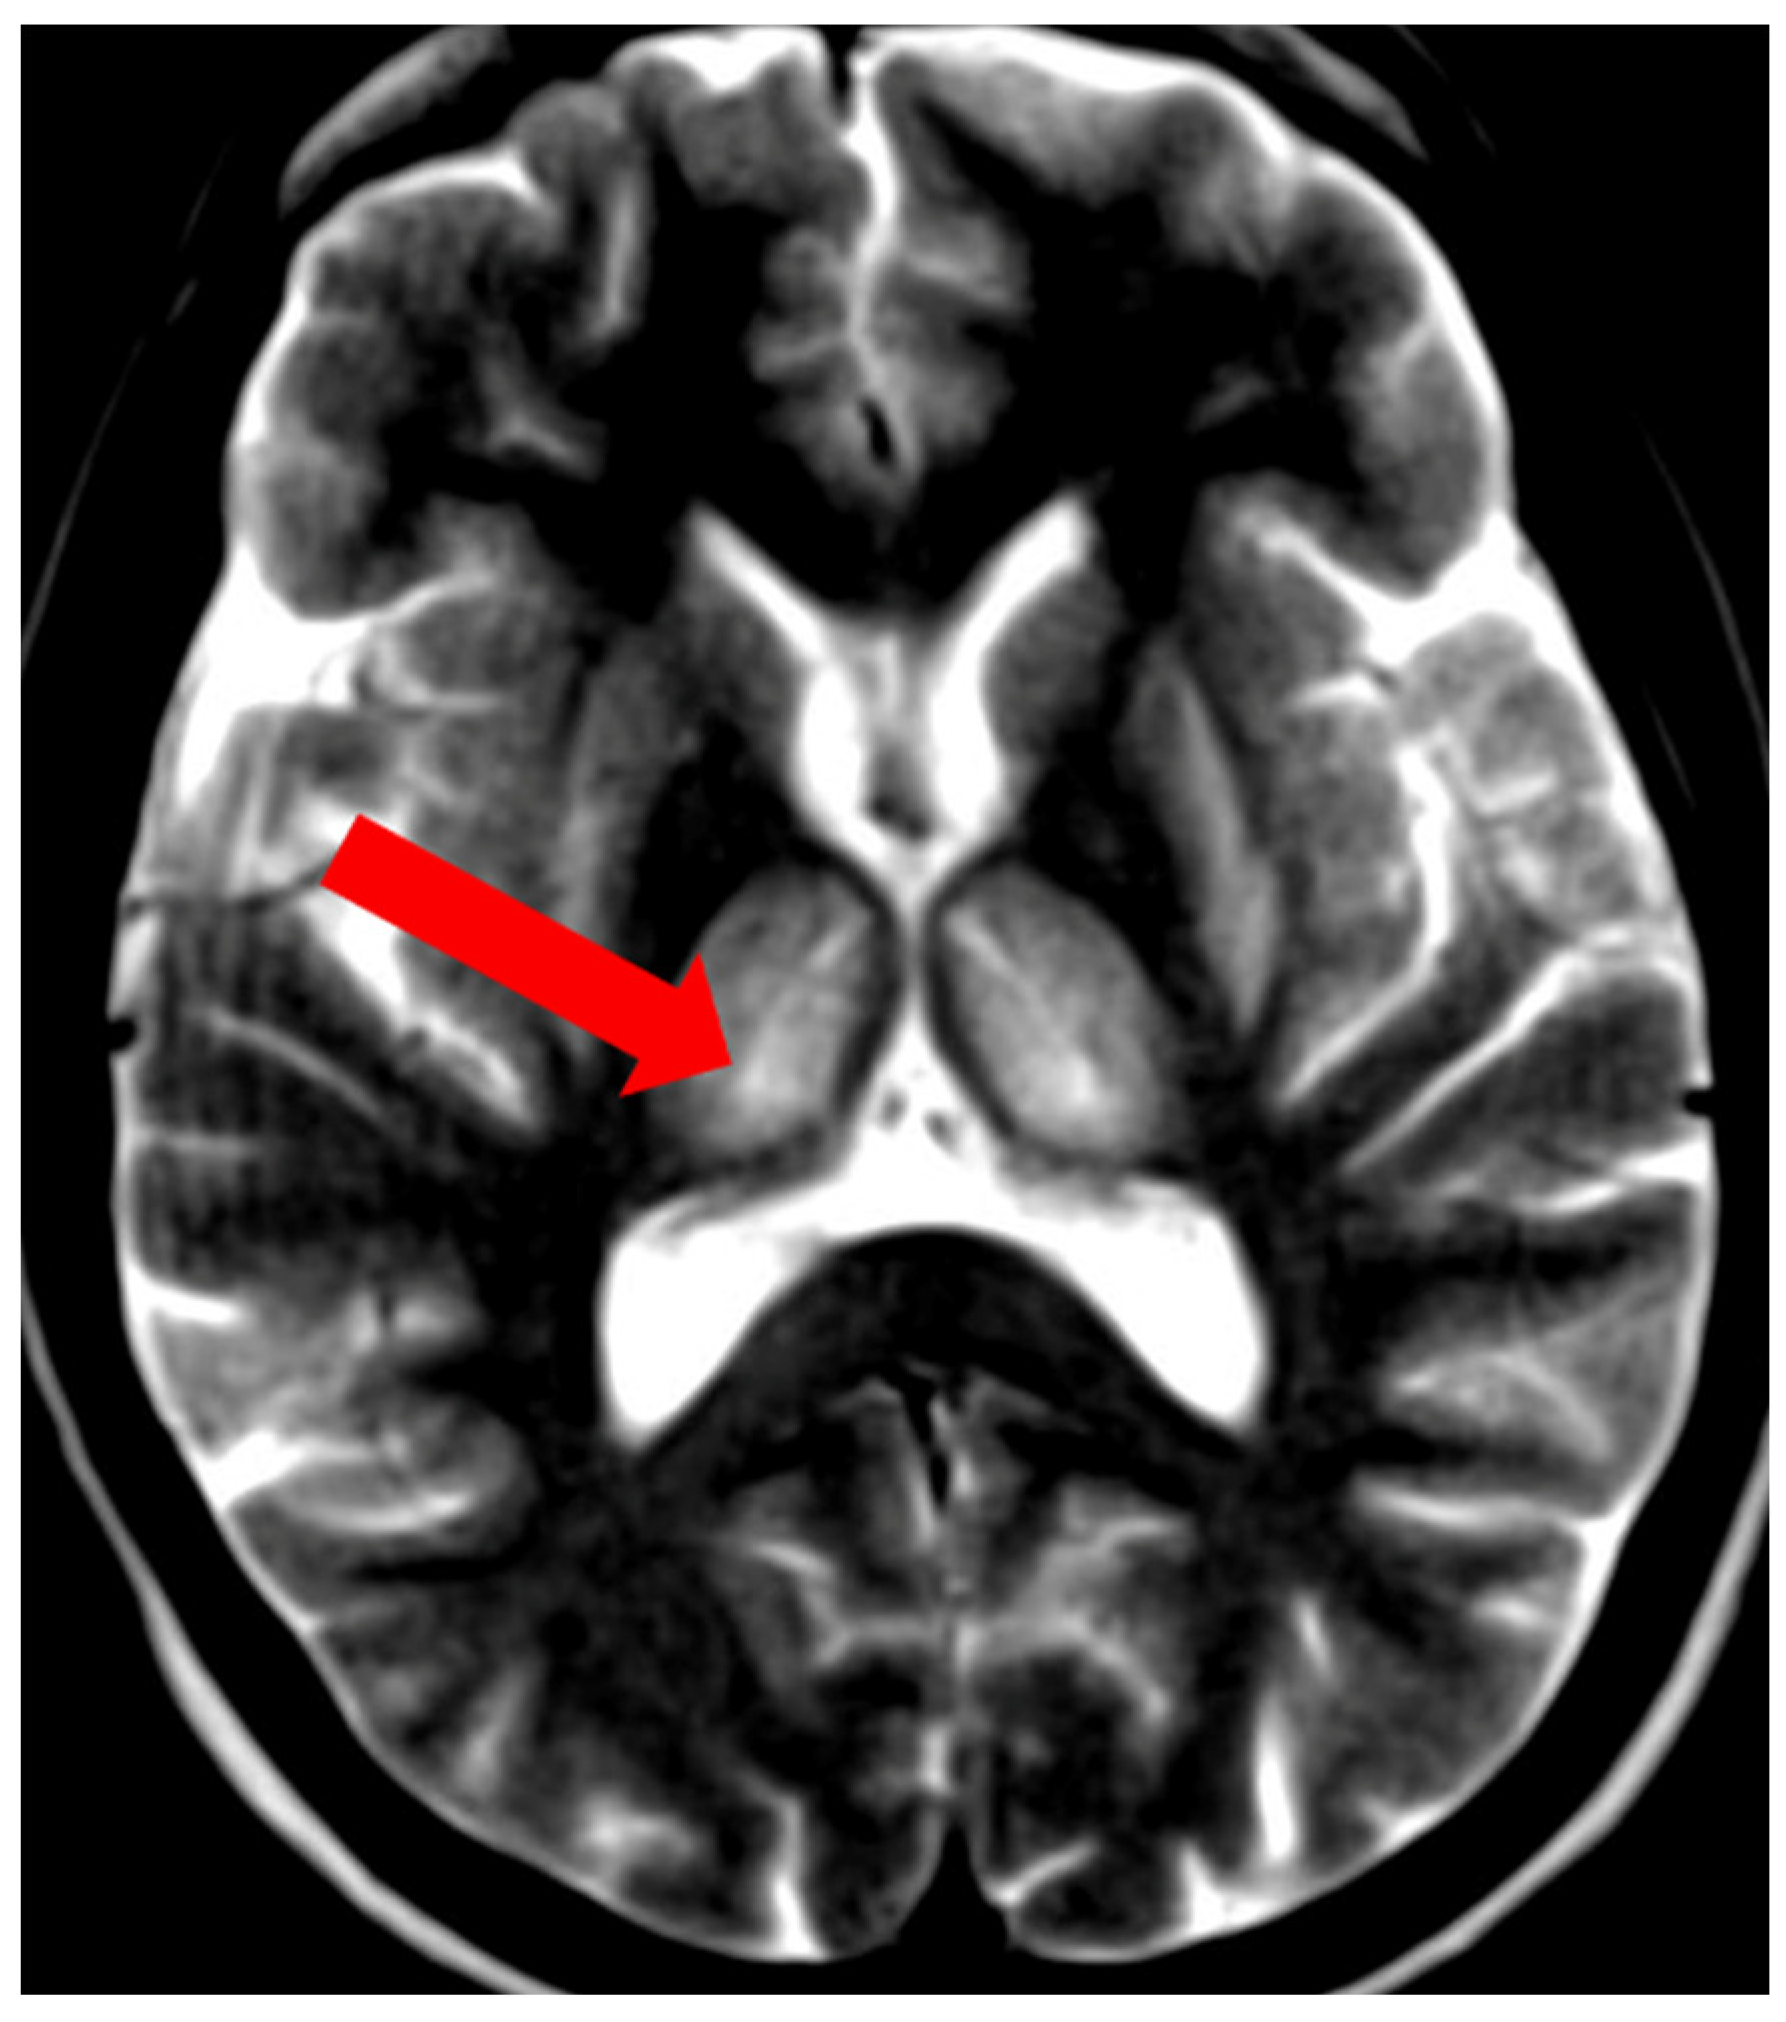

5. Neuroradiological Pathognomonic Signs of WD

- Hitoshi, S.; Iwata, M.; Yoshikawa, K. Mid-brain pathology of Wilson’s disease: MRI analysis of three cases. J. Neurol. Neurosurg. Psychiatry 1991, 54, 624–626. [Google Scholar] [CrossRef] [PubMed]